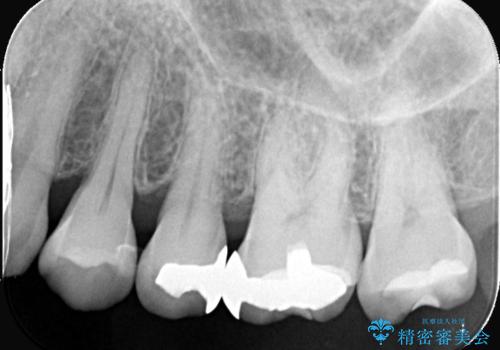

- 左上5番と6番の奥歯に入っている金属の詰め物(メタルインレー)の見た目を改善したいという主訴でご来院されました。お口の中の金属をなくしたいという患者様のご希望を踏まえ、天然歯に近い色と質感を持つセラミックインレーに交換する治療計画を立案。これにより、見た目の改善だけでなく、金属アレルギーのリスクを排除したメタルフリーの環境を実現することを目指しました。

治療では、まず古い金属のインレーを慎重に取り外しました。金属の下に隠れていた虫歯の再発がないかを確認し、歯を丁寧に形成。その後、精密な型取りから患者様の歯の色に合わせたオーダーメイドのセラミックインレーを作製しました。セラミックは、自然な光の透過性を持つため、周囲の歯と区別がつかないほどの美しい仕上がりとなります。適合性の高いセラミックインレーを装着することで、再発のリスクを抑えつつ、長年のコンプレックスだった銀歯がなくなり、笑顔でも気にならない自然な奥歯を取り戻していただけました。